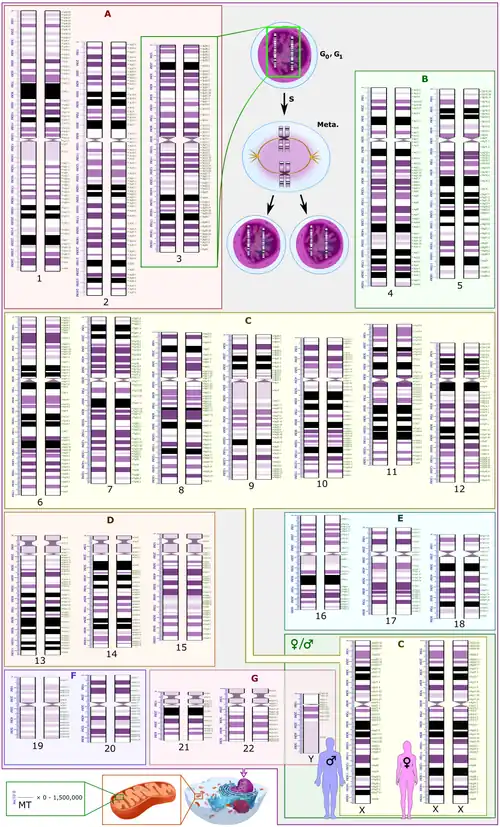

Human karyotype with annotated bands and sub-bands as used for the nomenclature of chromosome abnormalities. It shows dark and white regions as seen on G banding. Each row is vertically aligned at centromere level. It shows 22 homologous autosomal chromosome pairs, both the female (XX) and male (XY) versions of the two sex chromosomes, as well as the mitochondrial genome (at bottom left).

Human karyotype with annotated bands and sub-bands as used for the nomenclature of chromosome abnormalities. It shows dark and white regions as seen on G banding. Each row is vertically aligned at centromere level. It shows 22 homologous autosomal chromosome pairs, both the female (XX) and male (XY) versions of the two sex chromosomes, as well as the mitochondrial genome (at bottom left).

The International System for Human Cytogenomic Nomenclature (ISCN) is an international standard for human chromosome nomenclature, which includes band names, symbols and abbreviated terms used in the description of human chromosome and chromosome abnormalities. Abbreviations include a minus sign (-) for chromosome deletions, and del for deletions of parts of a chromosome.[55]